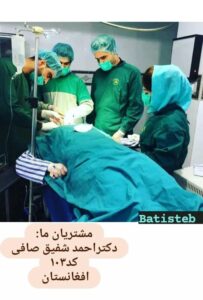

جالب است بدانید یکی از مشتریان ما که دارای مرکز حجامت بود اطلاعاتی را در مورد حجامت برای ما گذاشت که بسیار جذاب بود.

برآن شدیم اطلاعات مشتری را در اینجا قرار دهیم به امید گسترش صحیح حجامت در بین مردم علی الخصوص مسلمانان ایران به کمک تجهیزات نوین.